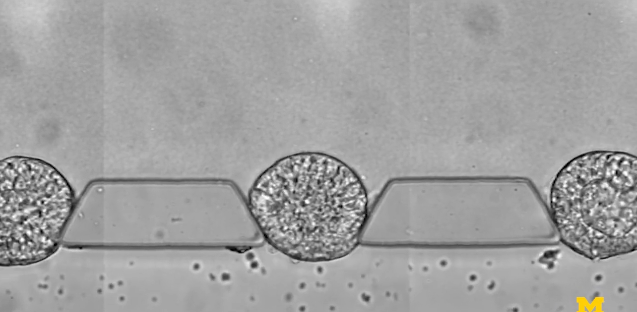

图 | 微流控芯片的特写照片,该芯片帮助干细胞组织成胚胎样结构,用于研究早期人类发育(来源:Fu Lab, Michigan Engineering)

研究人员由此开发出来一种微流体装置——由三个通道组成,分别用于放置细胞可嵌入的材料,装载干细胞,以及输运刺激干细胞分化的因子,借此研究人员能够控制干细胞在早期人类胚胎中面向主要细胞谱系的分化,可以可靠地产生数百或数千种类似胚胎的结构。

为了模拟胚胎着床后的发育阶段,即羊膜囊开始形成的时候,也是干细胞向分化成组织迈出第一步的时候,研究小组在一个可伸缩的三通道微流体系统中尝试培育干细胞。中央通道包含一种模拟子宫壁的凝胶,两侧有一个通道用于为干细胞补充营养,另一个通道用于递送引导。

剑平表示,“在传统的 3D 培养中,只有不到 5% 的干细胞簇会形成胚胎样结构。有了这个微流体系统,我们可以精确地控制培养环境,可以达到 90% 以上的效率来产生类似胚胎的结构?!?/span>